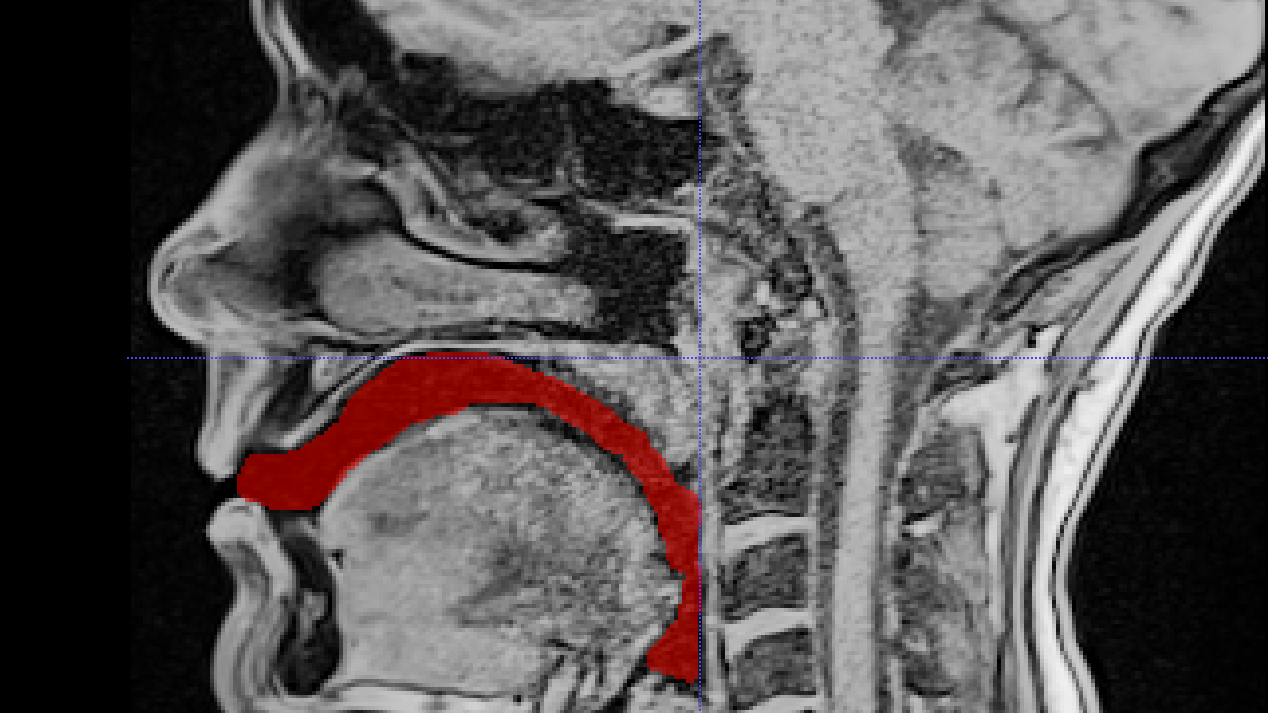

Conduits vocaux